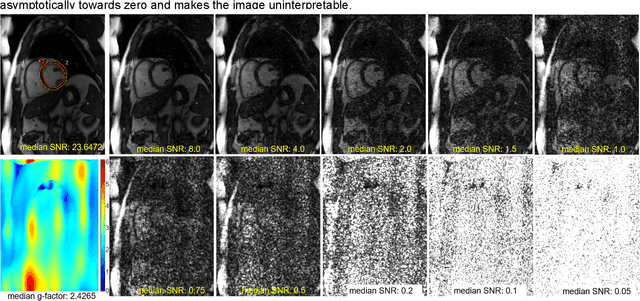

Abstract:Purpose: To propose a flexible and scalable imaging transformer (IT) architecture with three attention modules for multi-dimensional imaging data and apply it to MRI denoising with very low input SNR. Methods: Three independent attention modules were developed: spatial local, spatial global, and frame attentions. They capture long-range signal correlation and bring back the locality of information in images. An attention-cell-block design processes 5D tensors ([B, C, F, H, W]) for 2D, 2D+T, and 3D image data. A High Resolution (HRNet) backbone was built to hold IT blocks. Training dataset consists of 206,677 cine series and test datasets had 7,267 series. Ten input SNR levels from 0.05 to 8.0 were tested. IT models were compared to seven convolutional and transformer baselines. To test scalability, four IT models 27m to 218m parameters were trained. Two senior cardiologists reviewed IT model outputs from which the EF was measured and compared against the ground-truth. Results: IT models significantly outperformed other models over the tested SNR levels. The performance gap was most prominent at low SNR levels. The IT-218m model had the highest SSIM and PSNR, restoring good image quality and anatomical details even at SNR 0.2. Two experts agreed at this SNR or above, the IT model output gave the same clinical interpretation as the ground-truth. The model produced images that had accurate EF measurements compared to ground-truth values. Conclusions: Imaging transformer model offers strong performance, scalability, and versatility for MR denoising. It recovers image quality suitable for confident clinical reading and accurate EF measurement, even at very low input SNR of 0.2.